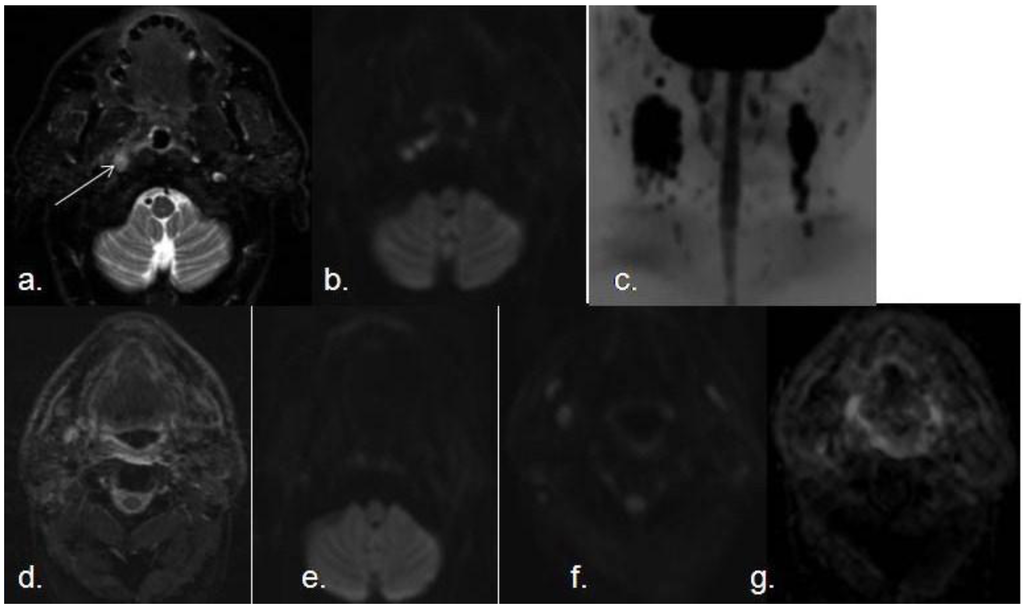

3.1. Detection and Evaluation of Primary Malignancies of the Upper Respiratory Tract and Malignant Lymph Nodes

- Sumi, M.; Sakihama, N.; Sumi, T.; Morikawa, M.; Uetani, M.; Kabasawa, H.; Shigeno, K.; Hayashi, K.; Takahashi, H.; Nakamura, T. Discrimination of metastatic cervical lymph modes with diffusion-weithed MR Imaging in patiens with head and neck cancer. AJNR Am. J. Neuroradiol. 2003, 24, 1627–1634. [Google Scholar]

- Kim, J.K.; Kim, K.A.; Park, B.W.; Kim, N.; Cho, K.S. Feasibility of diffusion-weighted imaging in the differentiation of metastatic from nonmetastatic lymph nodes: Early experience. J. Magn. Reson. Imaging 2008, 28, 714–719. [Google Scholar] [CrossRef]

- King, A.D.; Ahuja, A.T.; Yeung, D.K.; Fong, D.K.; Lee, Y.Y.; Lei, K. Malignant cervical lymphadenopathy: Diagnostic accuracy of diffusion-weighted MR imaging. Radiology 2007, 245, 806–813. [Google Scholar] [CrossRef]